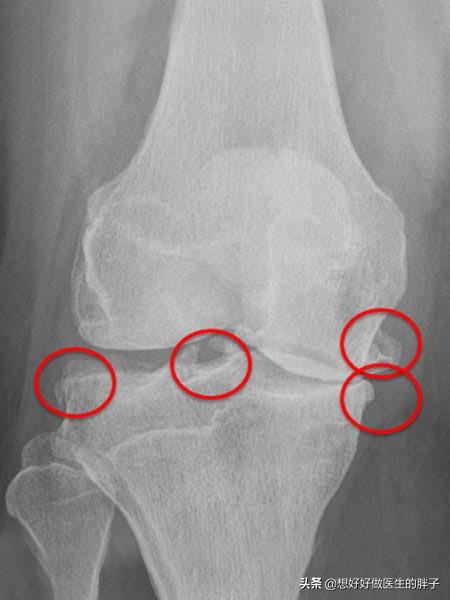

为什么有的人将骨赘称之为骨刺呢?就是因为有一些骨赘是突出骨骼范围之外的,其实这些骨赘比较小的时候,是不会对周边的软组织产生刺激和损伤的,但是如果当骨刺比较大以后,就有可能影响到周边的软组织、肌腱以及骨结构,从而产生疼痛、肿胀以及屈伸受限等症状。(下图的膝关节x线,患者就可能产生屈伸障碍、关节后方的疼痛或不适)

看到这里相信大家应该明白了,骨赘(骨刺、骨质增生)本来是帮忙的,之所以形成骨赘的基础是关节软骨的磨损,早期同时存在着纤维软骨修复、骨赘增生;晚期出现软骨的彻底破坏,表现为软骨硬化、软骨消失及软骨下局灶性骨坏死。晚期会导致严重的间隙狭窄和疼痛,需要手术解决大关节的问题。